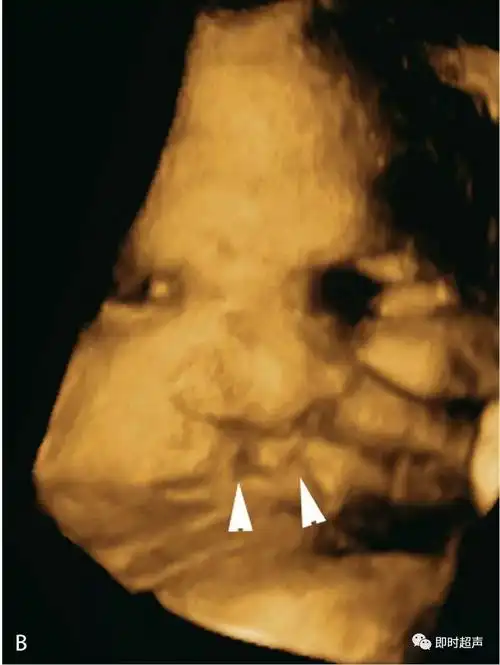

(b)同一胎儿的三维图像显示双侧唇裂(三角箭头).图6.1.

双侧唇裂 ,腭裂, 二维图片 三维图片